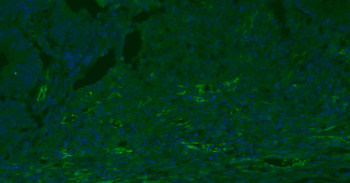

Immunofluorescense analysis of mouse lung tissue using anti-CD31 (primary antibody at 1:200)

IF analysis of mouse lung tissue using anti-CD31 (dilution of primary antibody at 1:200)